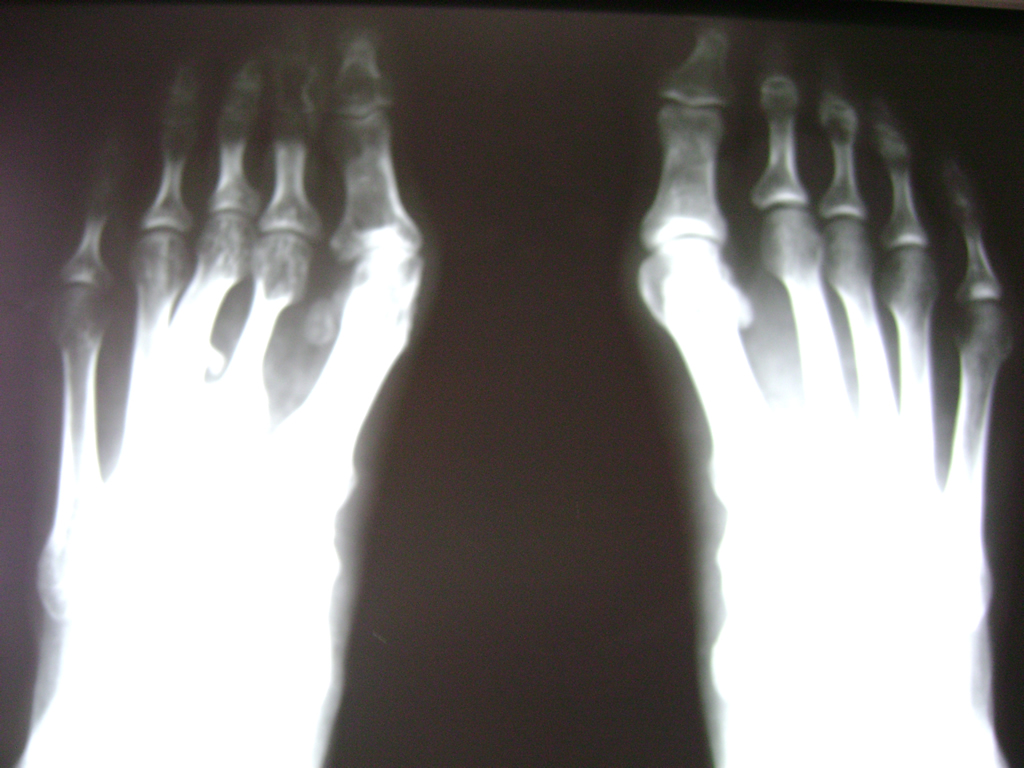

Cirugías de Pies

Las deformidades de los pies heredadas o adquiridas son el objeto principal de la cirugía reconstructiva del pie; sobretodo cuando producen dolor con el apoyo debido a una sobrecarga localizada o bien al no ser capaces de adaptarse a un calzado apropiado.

El pie consta de numerosas articulaciones con un mínimo movimiento cuya finalidad es adaptarse al terreno en cualquier situación. Cuando estas articulaciones que soportan grandes cargas y realizan movimientos sutiles se deterioran o funcionan de manera inapropiada, se suelen fusionar con el fin de evitar el dolor o bien restablecer la forma natural del pie y del apoyo.